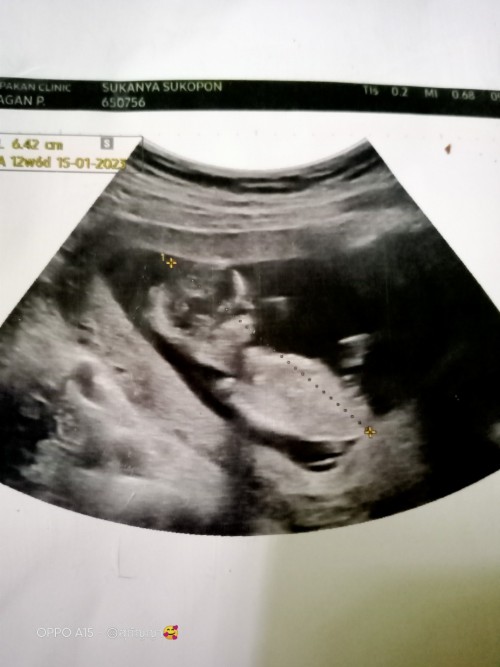

บ้านนี้กำหนดคลอด 15 มกราคม 66ค่ะ รูปนี้ซาวด์ตอน 8 วีคคะ 👶🏻💖